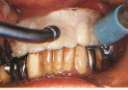

従来困難とされていた臼歯部のTEKは勿論(図13、14)、義歯を装着した症例にも応用が 可能である(図15〜17)。

図13.臼歯部使用例 図14.口腔内装着

図15.上顎;多数歯欠損、

下顎;義歯使用例

図16.義歯一体型のTEK(下顎) 図17.口腔内装着。下顎装着と同時に挙上

図18.旧義歯を使用した挙上例 図19.口腔内装着